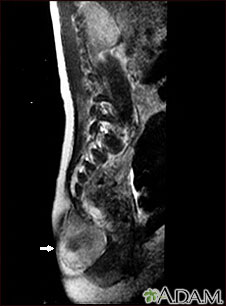

Esta IRM muestra un tumor (teratoma) en la base de la columna vertebral (se observa en el borde inferior izquierdo de la pantalla), situado en las áreas sacra y coxígea (área sacrocoxígea). Los teratomas se presentan al nacimiento y pueden contener pelo, dientes y otros tejidos.